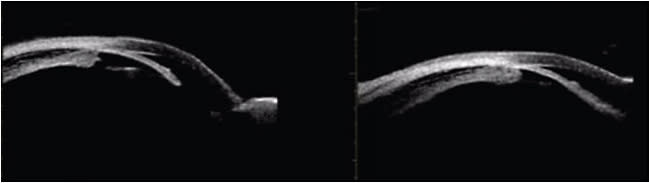

Given the high suspicion for topiramate-induced acute angle closure, we obtained an ultrasound biomicroscopy (UBM) image (Aviso A/B/UBM, Quantel Medical AG). This image demonstrated bilateral edematous and forwardshifting ciliary body and narrow angles, confirming our diagnosis (Figure 1).

First reported in 2012, topiramate-induced acute angle closure typically presents within the first 2 weeks of starting topiramate. Angle closure is thought to occur due to drug-induced changes in cellular membrane potential, leading to edema and forward displacement of the ciliary body. This both places pressure on the vitreous body and leads to a forward shift of the lens-iris diaphragm into the anterior chamber, narrowing and often closing the angle.5-8

Topiramate-induced acute angle closure presents with eye pain, redness, blurry vision and often nausea and vomiting. Exams show decreased visual acuity, a mid-dilated pupil, high IOP, shallow chamber and narrow or closed angles on gonioscopy. Diagnosis can be made by observing ciliary body effusion and forward rotation on UBM.